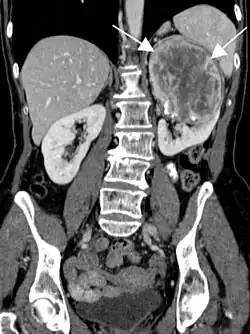

- Tumeur fibreuse solitaire du rein

Aspect tomodensitométrique. La tumeur est repérée par les flèches[46].

En tomodensitométrie[20],[31], quelle que soit la localisation, une tumeur fibreuse solitaire apparaît comme une masse tissulaire ovoïde ou lobulée, bien délimitée, refoulant les structures voisines sans les envahir. Elle se rehausse fortement après injection de produit de contraste. Les tumeurs de petite taille sont homogènes, mais les plus volumineuses présentent des plages hétérogènes de nécrose et d'hémorragie intra-tumorale. Il n'y a pas habituellement de calcifications et, lorsqu'elles sont présentes, elles sont de petite taille[31]. Les tumeurs malignes peuvent se présenter accompagnées de nodules pulmonaires métastatiques, et tendent à être plus volumineuses et plus hétérogènes[42].